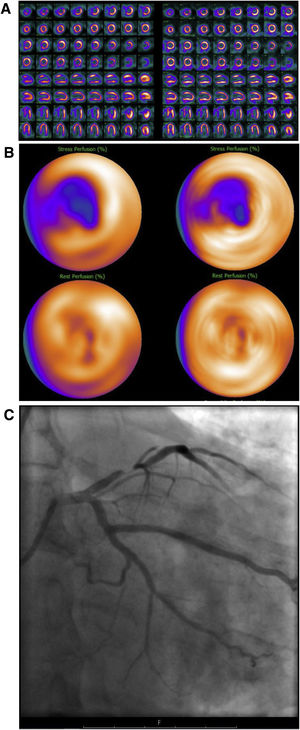

Mujer de 70 años, IMC 26, diabetes mellitus tipo II, fumadora, sin antecedentes cardiológicos previos. Diagnostico reciente de cáncer gástrico, se realiza una ecocardiografía como parte del estudio preoperatorio donde se observa una hipocinesis apical. Es remitida a IPM para descartar isquemia. Evaluación de la IPM sin SAPCA (imágenes en el lado izquierdo). IPM cortes de eje menor, de eje mayor vertical y eje mayor horizontal durante estrés en la fila superior y reposo en la fila inferior (A) y “ojo de buey” (B), mostrando un defecto de perfusión parcialmente reversible en la pared inferoseptal que afecta incluso el territorio apical. Mapa polar de imágenes gated durante el estrés mostrando contracción anormal moderada del ventrículo izquierdo (C). Ausencia obstrucción significativa de las arterias coronarias en la AC (D). IMP usando SAPCA (imágenes en el lado derecho) que muestran ausencia de defectos de perfusión significativos. La paciente pudo haber evitado la AC.

En consecuencia, la sensibilidad disminuyó del 94% sin SAPCA al 91% cuando se usa SAPCA, esto se debió a un mayor número de resultados falsos negativos (FN) cuando se usa SAPCA. Se encontraron 7 casos con resultados verdaderos positivos en la IPM confirmado con AC que convirtieron los resultados en FN cuando se evaluaron con SAPCA (fig. 2).

Mujer de 74 años, IMC 25, sin antecedentes cardiológicos previos. Presenta angina y electrocardiograma patológico. Es referida a una prueba de IPM para descartar isquemia. Evaluación de la IPM sin SAPCA (imágenes en el lado izquierdo). IPM cortes de eje menor, de eje mayor vertical y eje mayor horizontal durante estrés en la fila superior y reposo en la fila inferior (A) y “ojo de buey” (B), muestran un defecto de perfusión en la pared infero-septal, correspondiendo con el territorio de la arteria coronaria derecha, mostrando reversibilidad parcial en reposo. Obstrucción significativa de la arteria coronaria derecha comprobada con AC (C). IMP usando SAPCA (imágenes en el lado derecho) que muestran ausencia de defectos de perfusión significativos. Resultado falso negativo al usar SAPCA.